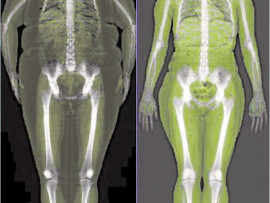

Motse’s Bone Vitality Centre in Richards Bay offers you a new technology called Duel-energy X-ray Absorptiometry (DXA), which accurately measures the whole body – its bones, muscular tissue and fat.

This low radiation exam can measure bone mineral density to determine the quality and density of the bones.

It also determines total body composition, measuring regional body fat, the relative skeletal muscle index, as well as resting metabolic rate.